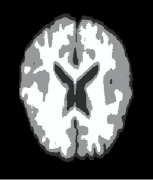

Example 3: real-world images. Test our method in two real-world images, i.e., camera man and MRI (magnetic resonance imaging) brain image which comes from medical imaging subject, see Fig. 4. We first test our method in noisy images and images with information lost. In Fig. 4, the variance used for adding noise is 0.01, and the percentage of information lost is . The conclusions we get are very close to those obtained when we test the methods in synthetic images in examples 1 and 2. From the rows one and three of Fig. 4, we see that all the methods give very good results in segmenting the two original real-world images. But for the images with information lost especially for the image in Fig. 4(A4), the results of methods [43, 23] are worse than the results of methods [6] and ours, see Fig. 4(B4), (C4), (D4), and (E4). Moreover, for the results of methods [6] and ours, we see that our result gives much more details for the white matter, see Fig. 4(D4) and (E4).

| (A4) | (B4) [43] (68.27) | (C4) [23] (74.28) | (D4) [6] (86.11) | (E4) Our (95.66) |